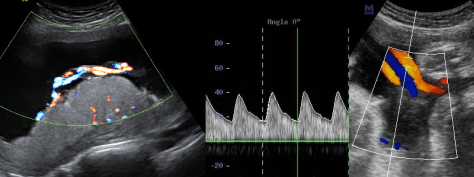

При скануванні ретельно оцінюються всі органі та системи: головний мозок, спинний мозок, обличчя, кістки, легені, діафрагма, серце, нирки, сечовий міхур, шлунок, кишечник, стінку живота, щоб діагностувати або виключити вроджені вади органів. Дослідження проводиться за допомогою кольорового та спектрального доплера, включно з ехокардіографією плода (УЗД серця плода).

При цьому також вимірюють розміри плоду та визначають його гестаційний вік і розвиток, оцінюють локалізацію, товщину та структуру плаценти, визначають кількость навколоплідної рідини, оцінюють довжину шийки матки. Дослідження триває 45 хвилин.

Для оцінки внутрішньоутробного стану плода, характеру та причин затримки розвитку плода, наявності гіпоксичних змін проводиться додаткове дослідження (доплерографія). Всі показники доплерографічного дослідження порівнюються в графічних таблицях та оцінюються відповідно гестаційному віку.

Дослідження проводиться за показанням, у вагітних високого ризику: оцінюється сума балів окремих біофізичних параметрів (дихальні рухи плода, тонус плода, рухова активність плода, об’єм навколоплодових вод). Додатково проводиться доплерографія кровоплину в пуповині і середній мозковій артерії плода, в маткових артеріях.